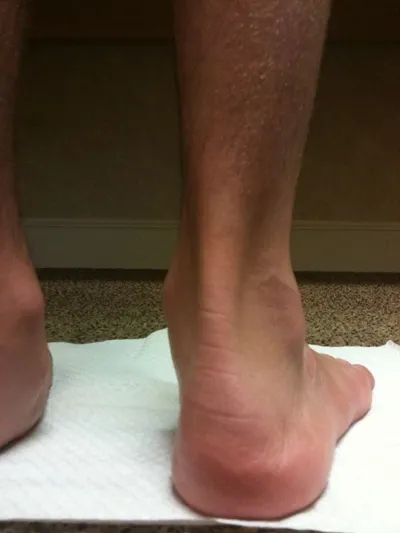

Clinical Pics of Patient

Below is a photograph of a patient before and after flat foot surgical correction with subtalar joint implant